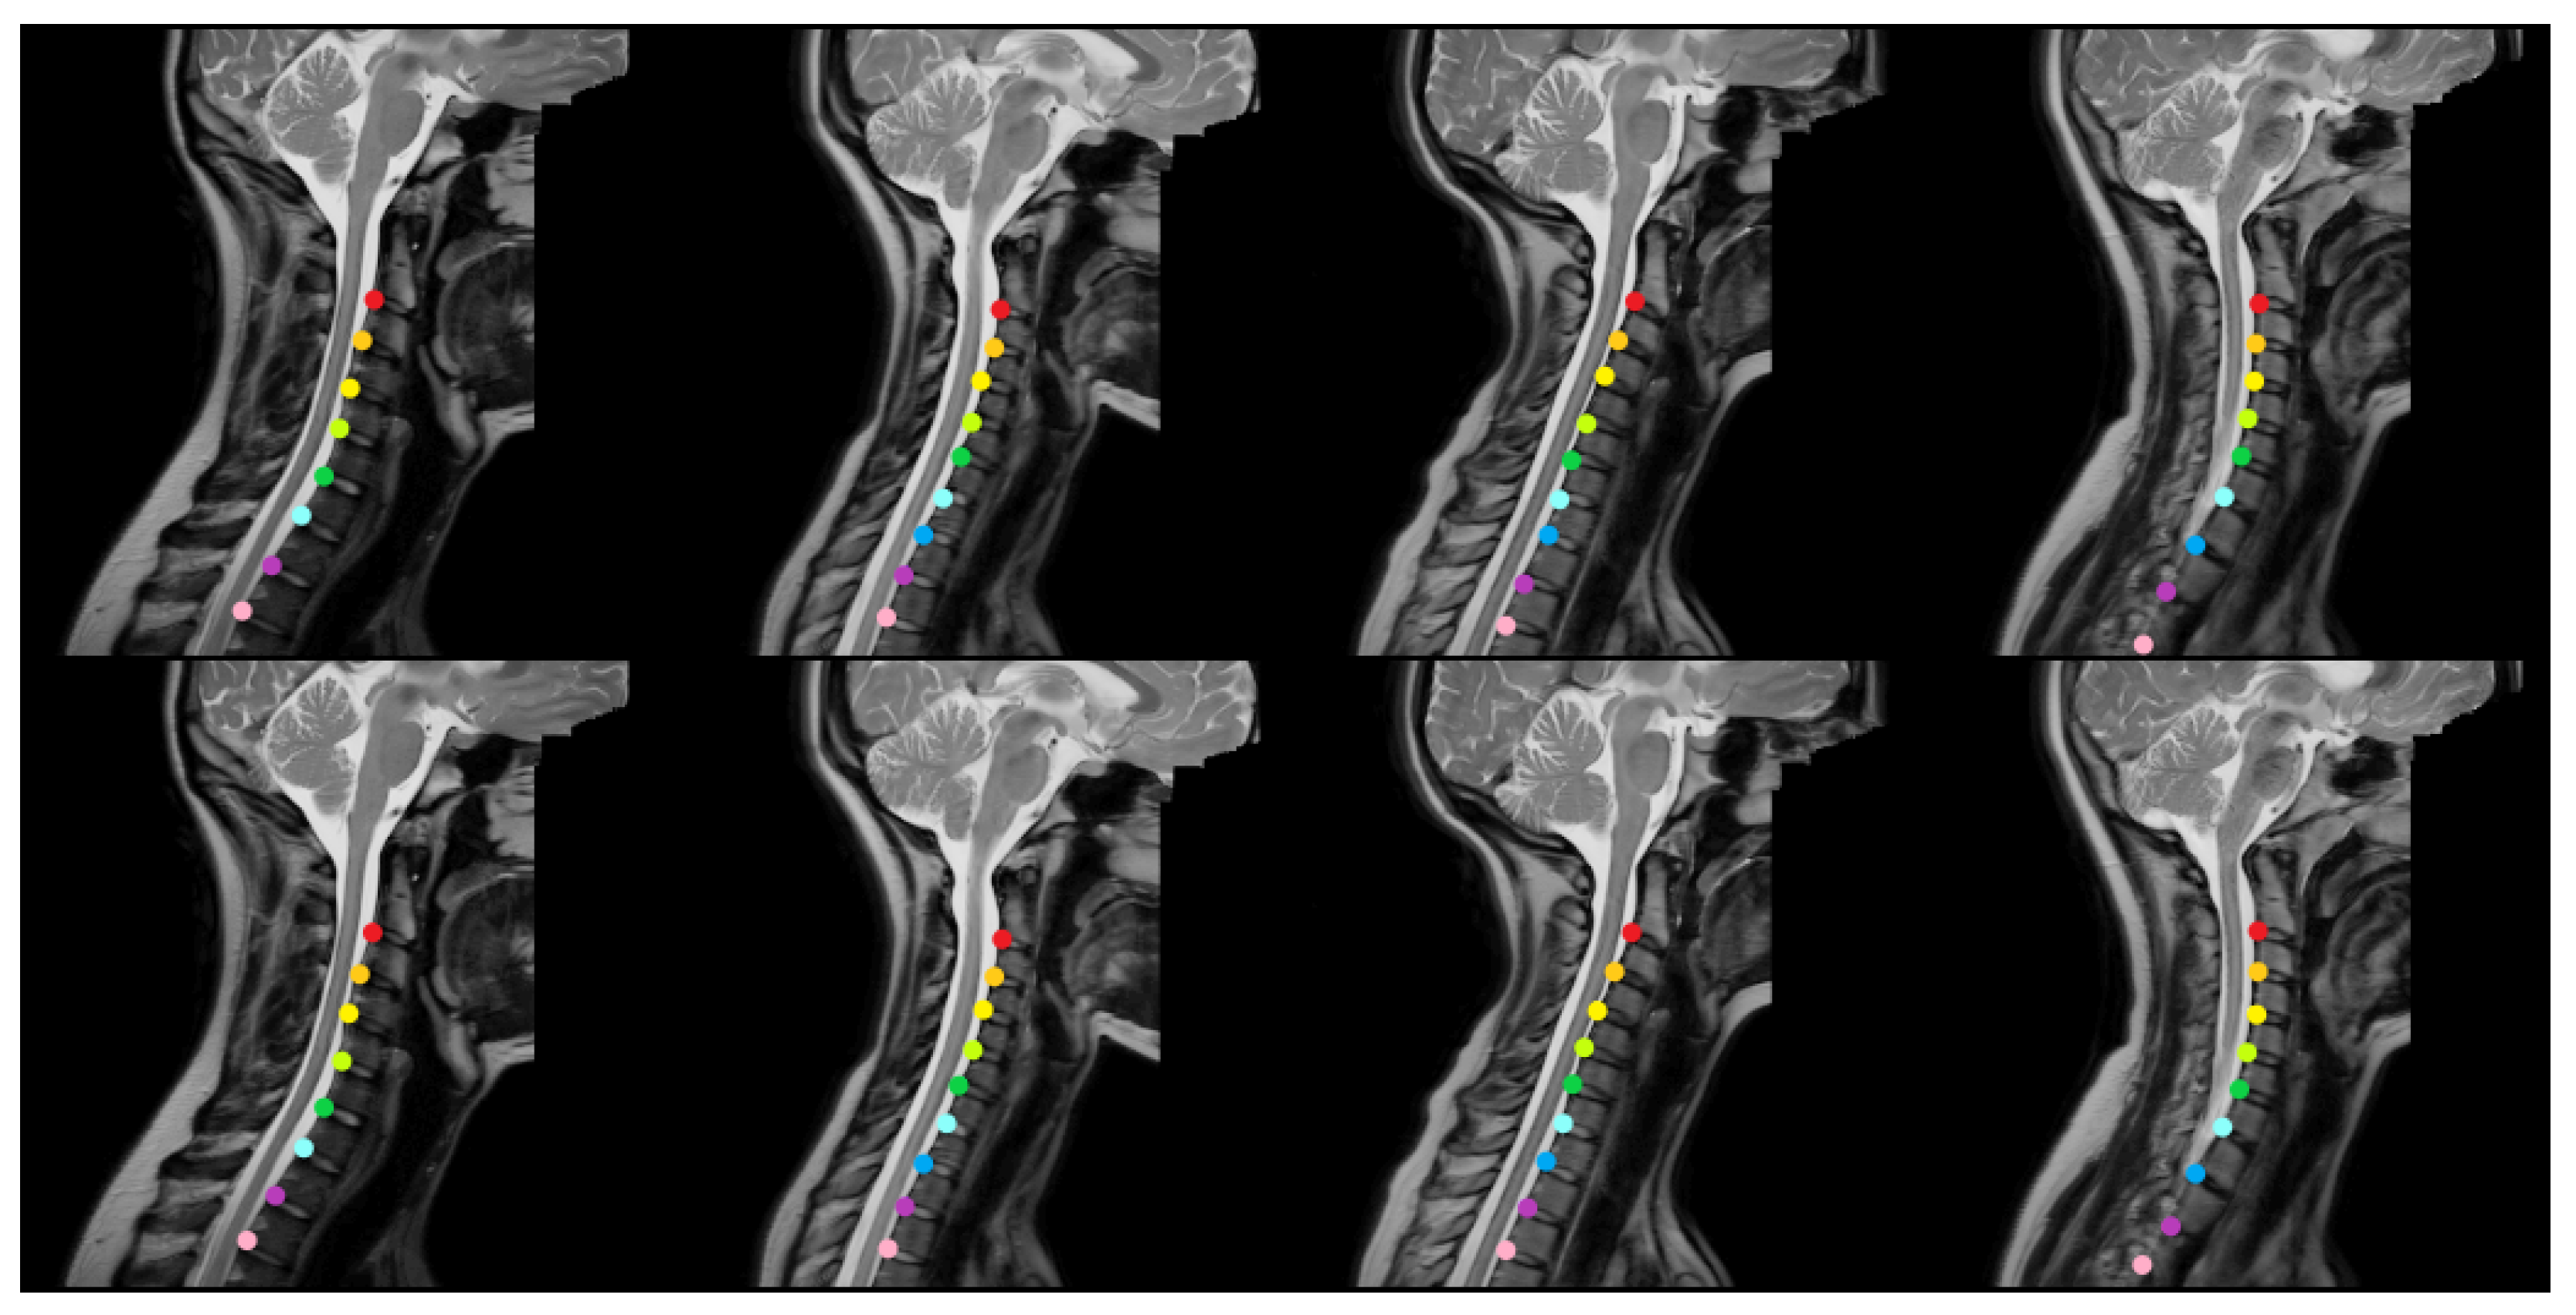

Figure 3 and Figure 4 provide representative qualitative results for MSA-Net on T1-weighted spine MRI. The predicted masks exhibit strong alignment with ground truth labels, particularly in the central disc regions. The model maintains tight localization even in images with low contrast or anatomical curvature. Notably, the method avoids common errors such as mislabeling vertebrae or merging adjacent discs, which were frequent in baseline models. In some cases involving pathological deformation or disc degeneration, minor under-segmentation occurs at disc boundaries. However, the predicted regions still provide accurate centroid locations, preserving the labeling task’s clinical value. These instances expose a limitation of the method, as it has not been explicitly trained to handle such anatomical extremes. Even in these challenging cases, our method maintains better performance than existing alternatives, demonstrating its robustness to anatomical variability.

Figure 3. The qualitative outcomes of the proposed approach for identifying intervertebral disc positions in MRI T1 scans. The model accurately predicts the location of each disc and visually distinguishes them using different colors based on semantic segmentation.